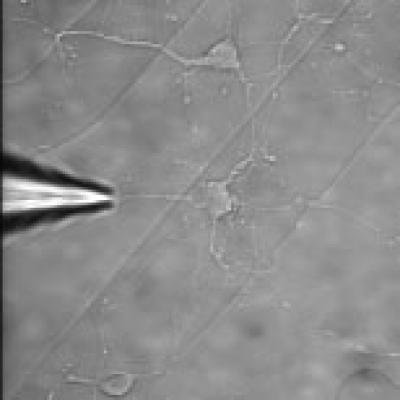

"What's new about this approach is that we didn't have to make the host cell pluripotent, that is the ability to develop into any of three major tissue types, we can directly convert from one cell type to another, without the intermediate step," explains Eberwine. The scientists put in an excess of astrocyte messenger RNAs into the neuron cell body using phototransfection, a method they created a few years ago that creates temporary pores in the cell membrane. "The RNA population was then diffused into the cell and the host cell did the rest," adds Eberwine.

Essentially the team extracted and produced mRNA from an astrocyte, then used phototransfection to create pores in the neuron cell membrane to flood it with an excess of astrocyte mRNAs, which reside in the neuron host cell cytoplasm. Because there are now so many astrocyte mRNAs versus neuron mRNAs, they take over like a virus and the astrocyte mRNAs are translated into astrocyte proteins in the cytoplasm. These astrocyte proteins then influence gene expression in the host nucleus so that astrocyte genes are turned on and astrocyte cell-enriched proteins are made.